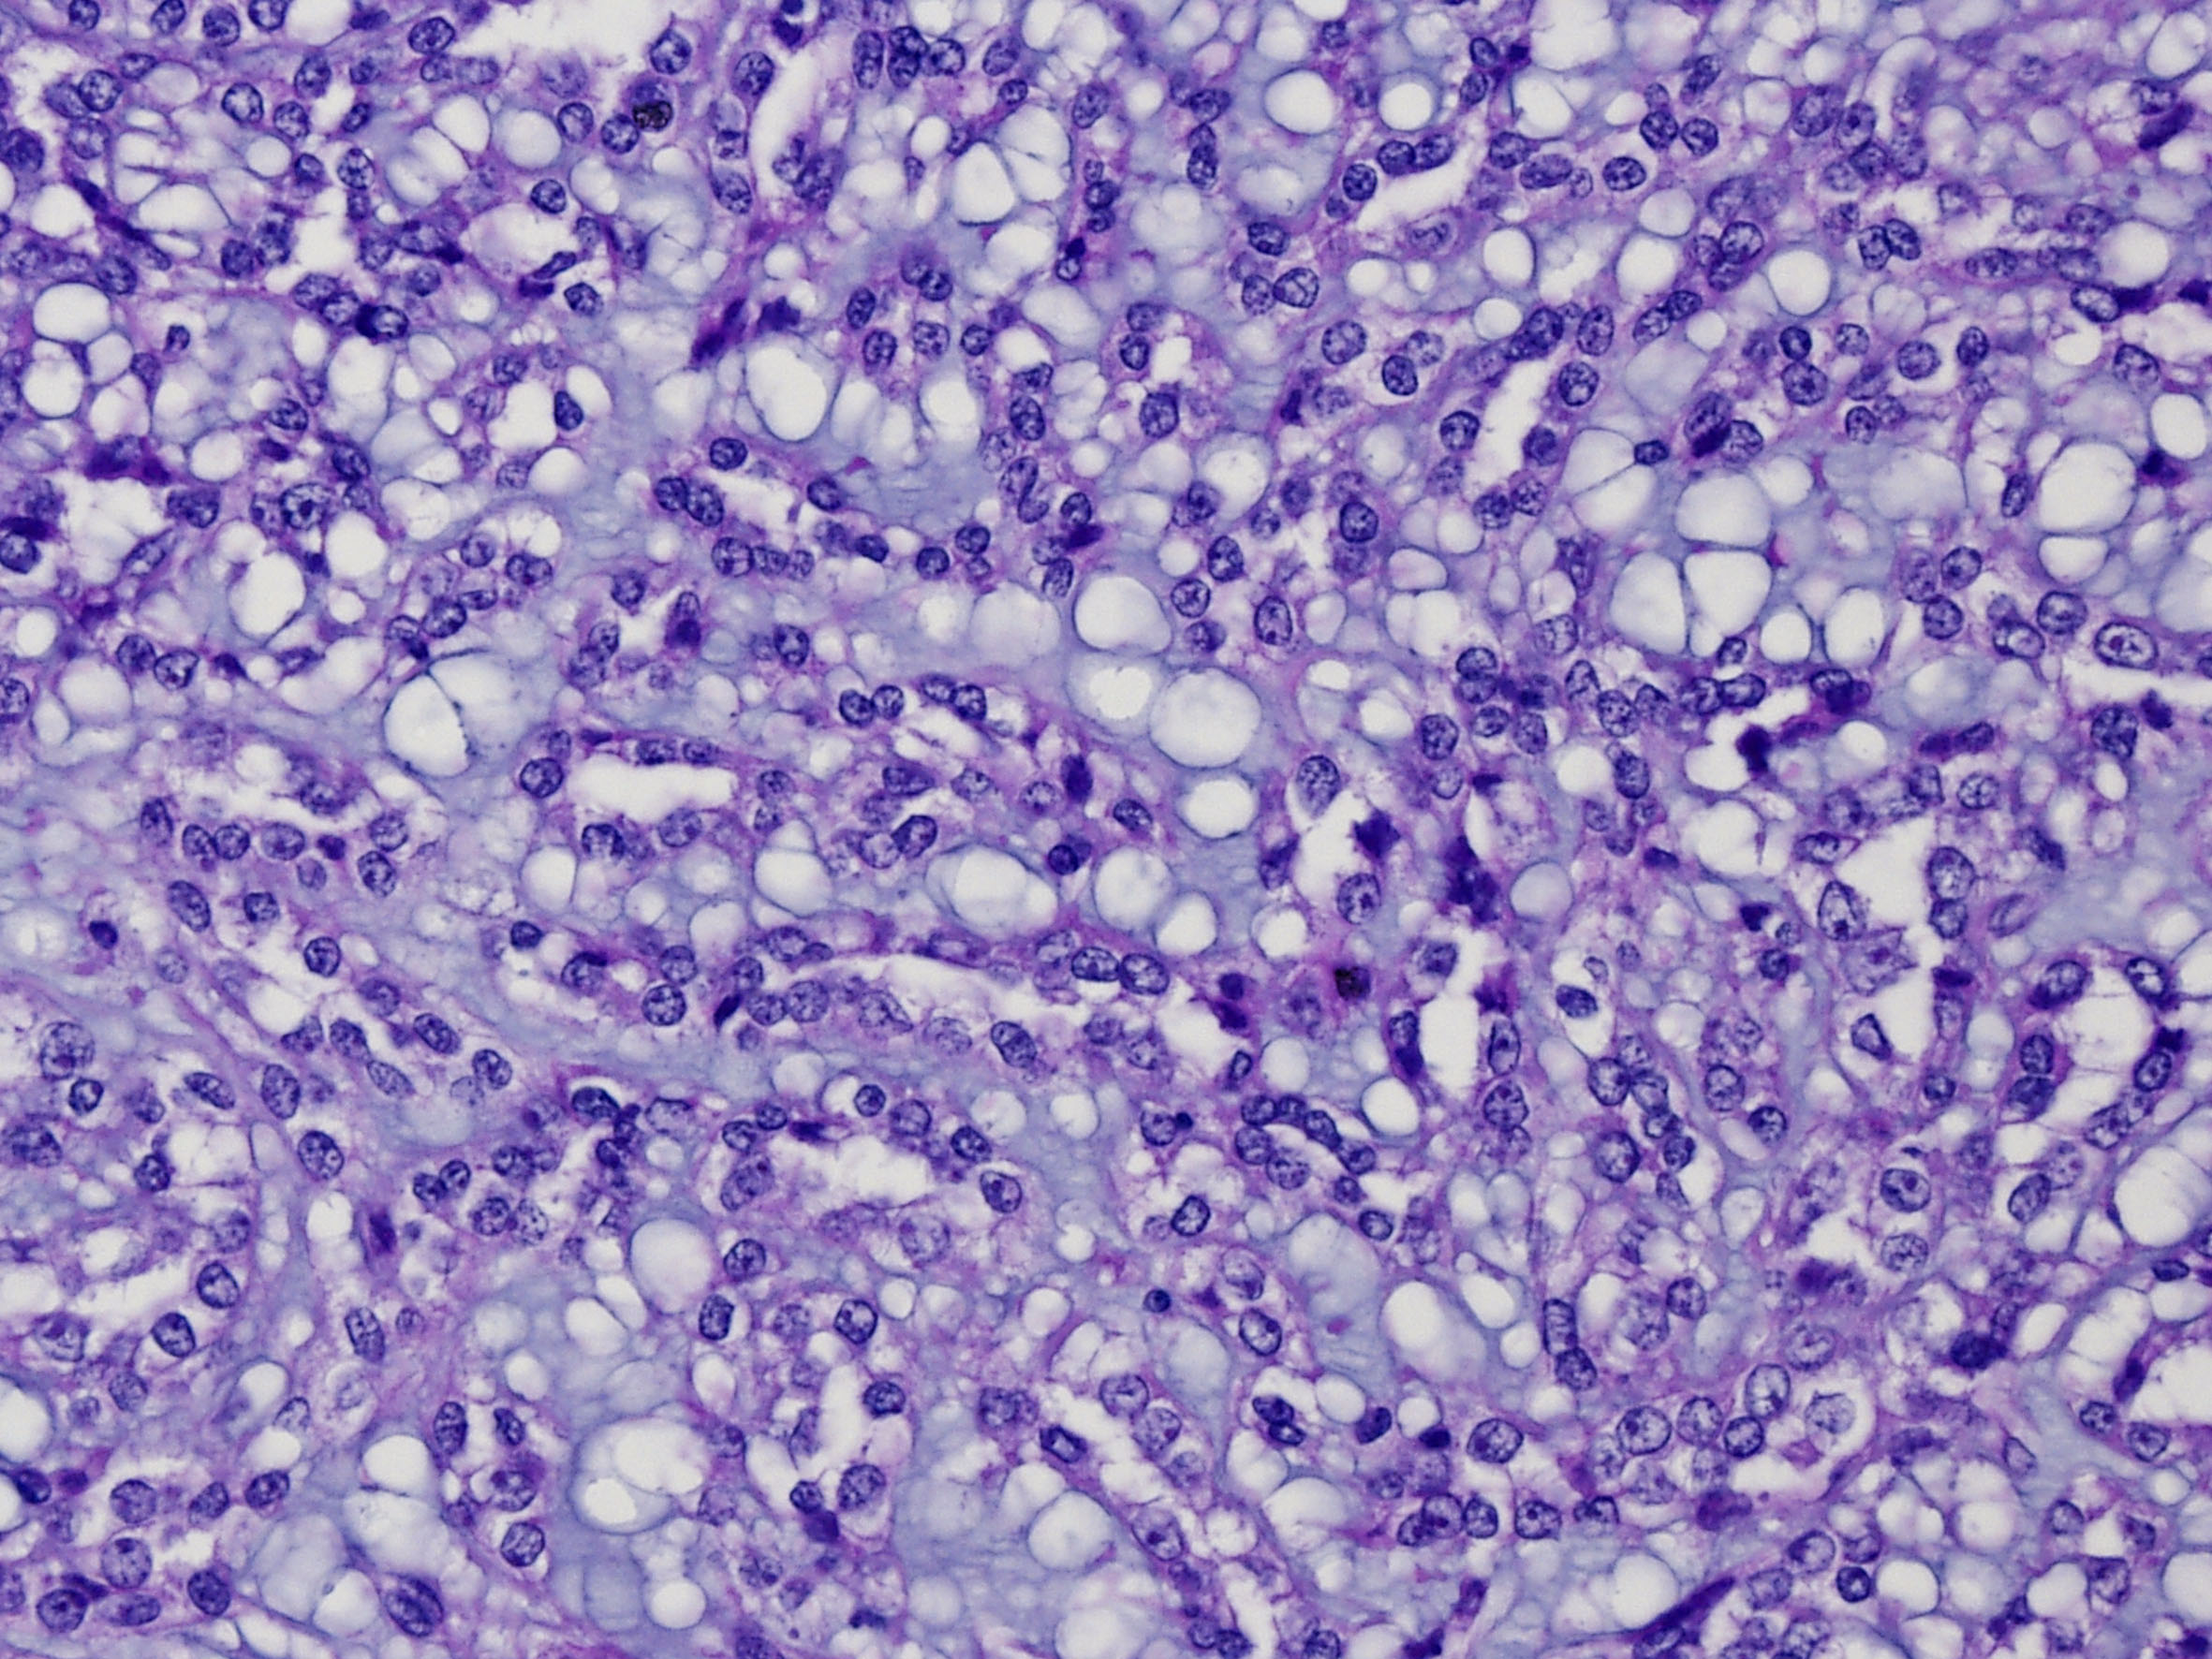

Classification of renal tumors

Case ID: 47